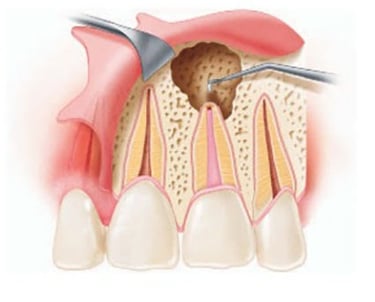

Es un procedimiento en el que se abre la cámara pulpar del diente para eliminar el tejido pulpar infectado o inflamado. Esto ayuda a aliviar el dolor y preparar el diente para un tratamiento de conducto.

Trepanación Pulpar (urgencia)